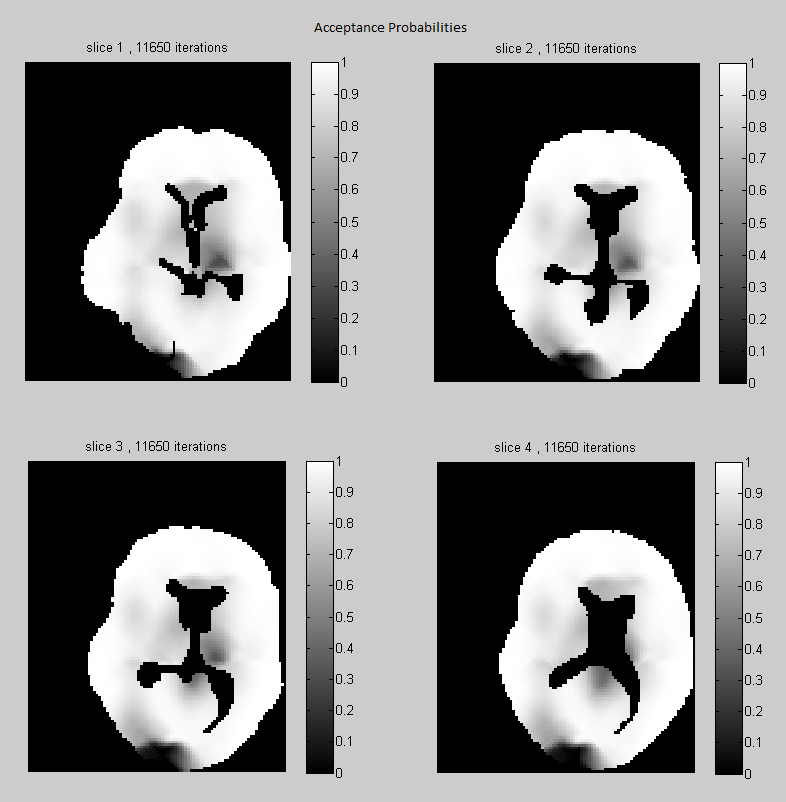

Acceptance probabilities

In Fig. 3 we show the acceptance probabilities for the Gibbs-Metropolis block update of the tensor parameters, estimated for each voxel under the regularized 2nd and 4th order tensor models. Note that, although we use large block updates with more than 300 voxels in each block, the acceptance probabilities are remarkably high in most of the voxels (see the histograms). It means that in most cases the our Gaussian approximation is very close to the exact full conditional distribution of the tensor parameters in a block. Note also that in Fig. 3(a) (which corresponds to 2nd order tensor model) there are some regions with lower acceptance probability. In such areas one should use update blocks of smaller size. These regions of lower acceptance probability are either artefacts, where the data are corrupted, or contain complex structures where the 2nd order tensor model does not fit well the data, and a higher order model would be more appropriate. We see two low acceptance probability regions situated symmetrically on the left and right sides of the ventricles. Anatomically this corresponds to the corona radiata where fiber bundles from multiple directions are crossing. By comparing with Fig. 3(b) we see that in these regions the acceptance probability improves under the (regularized) 4th order tensor model. For the diffusion model without regularization, the independent tensor updates have high acceptance probabilities at all voxels, under both 2nd and 4th-order tensor models (in 5).